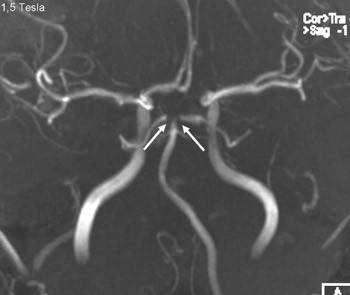

Figure 2

A person in his 20s with known migraine with aura developed infarcts in the right middle cerebral artery and both anterior fields of supply (Figure 1 shows a magnetic tomography diffusion weighted series). Cerebral computed and magnetic tomography with magnetic resonance angiography (MRA) after admission showed normal blood flow and no sign of dissection or vasculitis. Hemicraniectomy became necessary after development of malignant cerebral oedema. MR angiography the first postoperative day showed open arteries (Figure 2 shows an open carotid top (white arrow), normal basilar top (red arrow), and a non-closed circle of Willis, an anatomically normal variant (stars). Testing for illegal drug use, anticardiolipins, anti-nuclear antibodies, neurone antibodies and tumour markers was negative. Transoesophageal echocardiography showed a minimally patent foramen ovale, according to a cardiologic evaluation unlikely to be related to the episode. The patient developed severe brain stem involvement and MR angiography showed narrowing of the posterior branch of the basilar artery (arrows in Figure 3). Arterial vessel spasms were suspected retrospectively. The first suspected vessel spasm, in the right – middle/anterior branch, remained undocumented. The second, in the posterior branch of the basilar artery, was documented postoperatively (arrows in Figure 3). Images of several newly developed infarcts in the posterior circulation are not shown. Three weeks after the hemicraniectomy the angiogram was normalised (Figure 4).